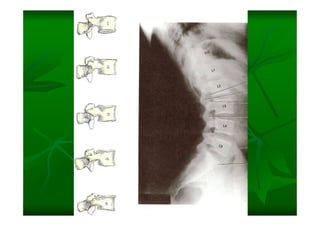

Este documento describe la columna vertebral humana. Está compuesta de 33 vértebras divididas en 7 cervicales, 12 torácicas, 5 lumbares, 5 sacras y 4 cóccigeas. Cada vértebra posee un cuerpo, pedículo, apófisis transversas, apófisis espinosa e inferior y laminas. Las curvaturas de la columna son la lordosis cervical y lumbar y la cifosis torácica y sacra.